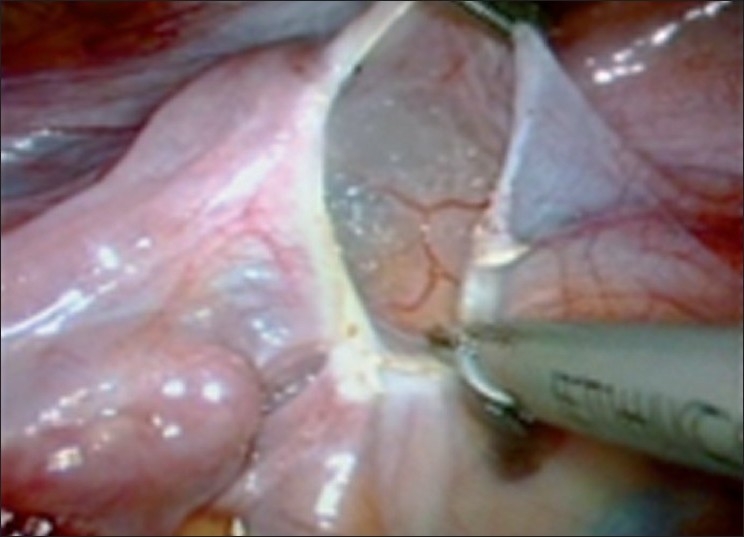

Most of the surgeons find it difficult to perform myomectomy when it bleeds during the procedure as it becomes difficult to get into the correct plane of dissection. If this bleeding or blood staining of tissues is prevented it will be easier to get into the correct plane of dissection. In several studies, it is found that bilateral uterine artery ligation, at origin, does not interfere with future fertility as the end vessels and collaterals of the uterus are not interfered with. As no energy source is used to incise the myoma once Vasopressin has been used, the myomectomy scar integrity is better, as noted by various surgeons.